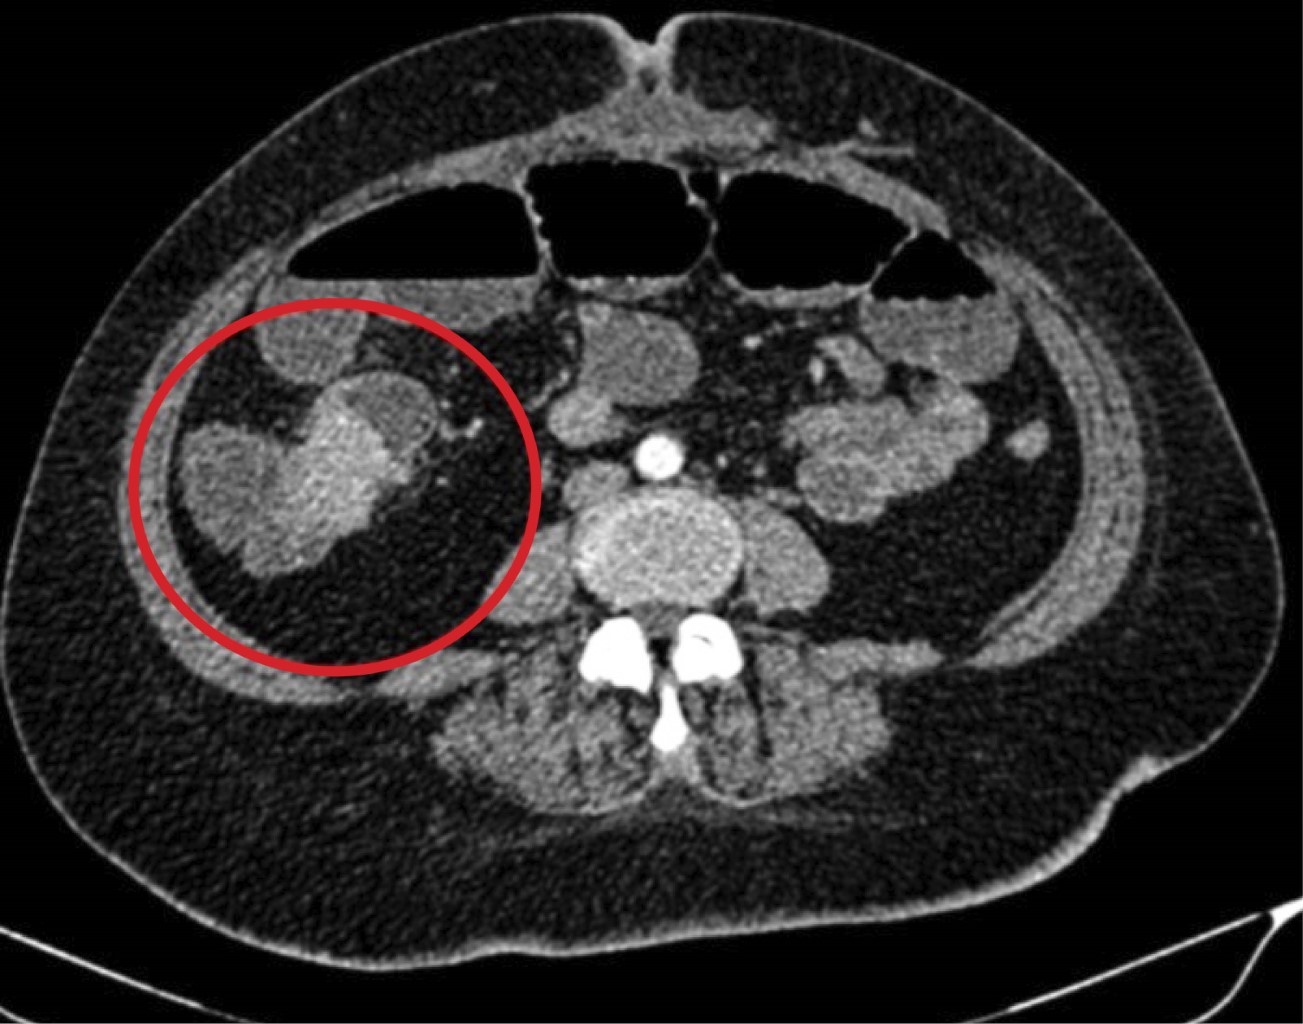

Se inició abordaje diagnóstico, se realizaron estudios de laboratorio y se obtuvieron cifras de leucocitos 9.08 × 103/mm3, hemoglobina 8.9 mg/dL, plaquetas 408 × 103/mm3, proteína C reactiva 42.4 mg/L. Se complementó el abordaje con estudios de gabinete, se inició con radiografías de abdomen, observando datos de oclusión intestinal tales como múltiples niveles hidroaéreos y ausencia de gas distal. Ante tales hallazgos, se decidió realizar tomografía de abdomen, la cual reportó obstrucción intestinal, sin descartar origen neoplásico con ganglios centinelas mesentéricos (Figuras 1 y 2).

Ingresó con diagnóstico de oclusión intestinal secundaria a tumoración en estudio, para realizar laparoscopía diagnóstica a proceder. Dentro de los hallazgos quirúrgicos se evidenció dilatación importante de asas de intestino delgado con zona de transición a nivel de íleon terminal, se observó una masa a nivel del mesenterio de íleon terminal (Figura 3A y B).

El diagnóstico preoperatorio es muy complicado. Los hallazgos por tomografía suelen ser muy inespecíficos, dentro de lo que se suele observar por este método de imagen son masas hipodensas con un realce periférico a la administración de medio de contraste, es imposible hacer un diagnóstico con certeza a menos que se identifique el pedículo vascular torcido en caso de una torsión. Mediante ultrasonido los hallazgos suelen ser una masa bien definida, hipoecoica y homogénea, y que mediante ultrasonido Doppler se confirma su estado avascular en caso de torsión, sin embargo, no se puede distinguir de un quiste. La resonancia magnética también es un método útil para el diagnóstico, pero poco utilizado debido al contexto de urgencia en el que se suele realizar el abordaje diagnóstico.4 Es de suma importancia ante la sospecha de un bazo accesorio la identificación del bazo principal previo a la resección del bazo accesorio. En nuestro caso se reporta por tomografía una masa sin lograr descartar patología neoplásica.